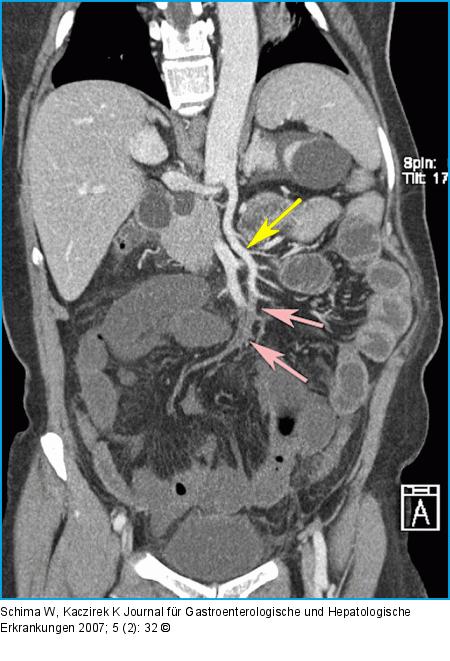

Abbildung 1B: 3D-Rekonstruktion der CT Die 3D-Rekonstruktion der CT entlang der A. mes. sup. zeigt viel anschaulicher den offenen proximalen Abschnitt der A. mes. sup (schwarzer Pfeil) und den embolischen Verschluß distal (weiße Pfeile). |